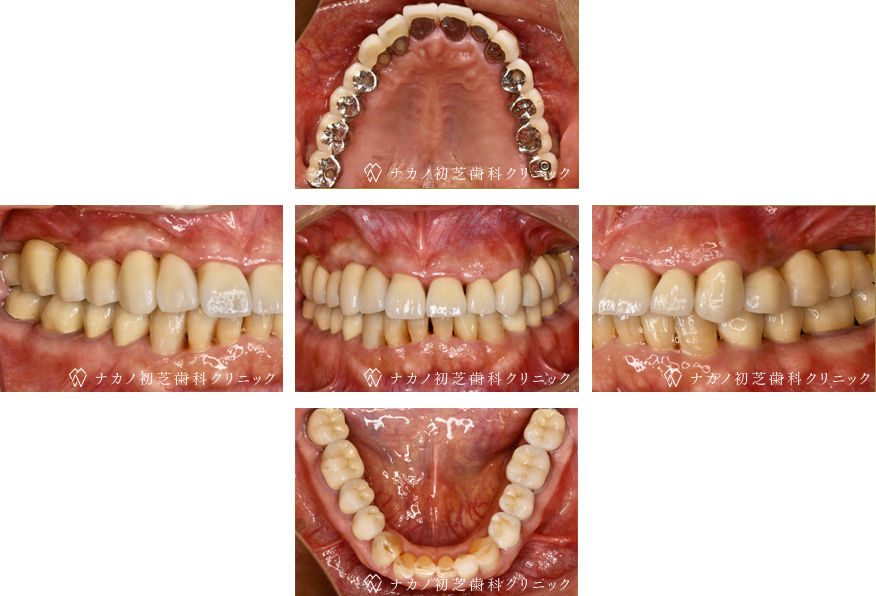

インプラント・7本 (60代男性)

-

BEFORE

AFTER

年齢 60代男性

治療内容 インプラント治療7本(骨造成の併用)

インプラント治療とは、歯を抜いた所にチタン製の人工歯根を埋入し、その上に歯を入れる方法です。骨を増やすことで、より審美的に治療が出来ました。費用 1本 400,000円(税込 440,000円)

リスク・副作用

腫れ・疼痛・違和感を感じるなどの症状を生じることがあります。